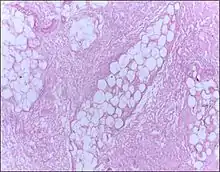

![]() | Lipoma | Micrograph of a lipoma showing fat cells. | Category: Histopathology of lipomas | Lipoma |